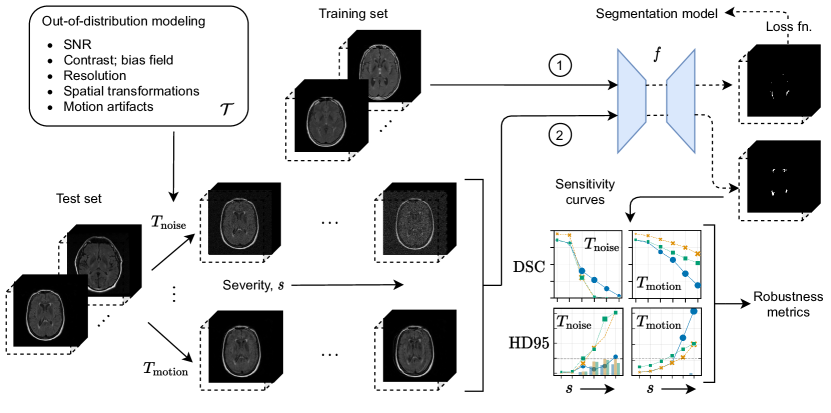

Refer to caption

Figure 1: Methodology overview for benchmarking robustness to OOD data and corruptions. A segmentation model f𝑓f is first trained on the clean training set (path 1). The test set is expanded by applying OOD-modeling transforms Ti𝒯subscript𝑇𝑖𝒯T_{i}\in\mathcal{T} to each sample, with defined severity levels s𝑠s for each transform (path 2). The trained segmentation model f𝑓f generates predictions on each transformed test sample, yielding robustness metrics used for benchmarking. SNR: signal-to-noise ratio; DSC: Dice similarity coefficient; HD95: modified (95th-percentile) Hausdorff distance.

We simulate distribution shifts and corrupted data by applying transforms to images from a clean test set (Figure 1). We refer to the transformed test set as a benchmarking dataset. As shown in Figure 2, we selected 11 different transforms that cover distribution shifts across multiple categories discussed previously: (1) signal-to-noise ratio (SNR); (2) contrast and intensity non-uniformity; (3) image resolution and blurring; (4) spatial location of features (e.g., translations, rotations, deformations); (5) presence of motion artifacts. Ground truth segmentations were transformed accordingly and re-discretized for spatial transforms that alter the shape or orientation of the feature of interest (e.g., affine, elastic deformation, downsampling). Transforms were sourced from the Medical Open Network for AI (MONAI)222https://monai.io/ and TorchIO333https://torchio.readthedocs.io/ [Pérez-García et al., 2021] libraries, both part of the PyTorch Ecosystem [Paszke et al., 2019], or implemented where implementations were unavailable (e.g., for MRI [Rician] noise). See A for full descriptions of each transform and their formulations.